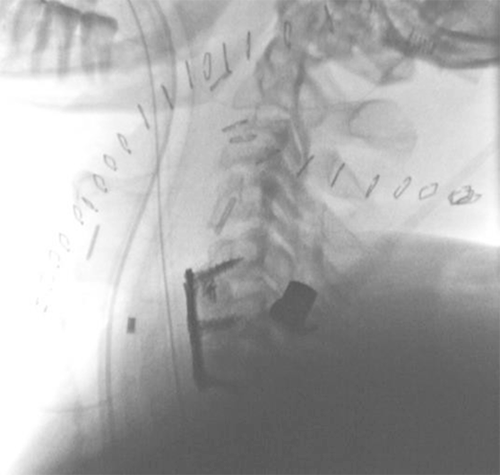

During exploration, the patient had persistent desaturations and remained hypotensive, and bilateral chest tubes were placed with no hemothorax or pneumothorax appreciated. Our operative exploration continued with a posterior extension of the primary incision to evaluate the posterior triangle of the right neck, where active hemorrhage was appreciated. Intermittent occlusion by a balloon catheter was used during dissection, and local hemostatic packing agents were applied after further localizing bleeding. Dissection was carried to the cervical spine, which appeared to be disrupted at this level. The proximal and distal ends of what appeared to be the transected right vertebral artery were identified and clipped. Bone wax and oxidized cellulose-based hemostatic agent were used, achieving hemostasis. The patient was hemodynamically stable at this time, and the decision was made to proceed to interventional radiology for angiography and possible embolization. The wound was temporarily packed and closed with staples. The angiography demonstrated a right vertebral artery dominant pattern with occlusion of its proximal end consistent with our surgical clip placement. The patient's left vertebral artery and posterior circulation were intact, including the right posterior inferior cerebellar artery. The proximal end of the right vertebral artery was embolized. The clips were adequately occluding the distal end of the vertebral artery (Figure 1).

Figure 1. Angiogram of Bilateral Vertebral Arteries (VA). Published With Permission

Right VA angiogram with proximal cut-off and subsequent embolization (blue arrow). Left VA angiogram without injury (green arrow) and intact circle of Willis (purple arrow).